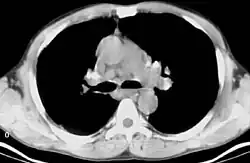

Bilateral hilar lymphadenopathy

Bilateral hilar lymphadenopathy is a bilateral enlargement of the lymph nodes of pulmonary hila. It is a radiographic term for the enlargement of mediastinal lymph nodes and is most commonly identified by a chest x-ray.